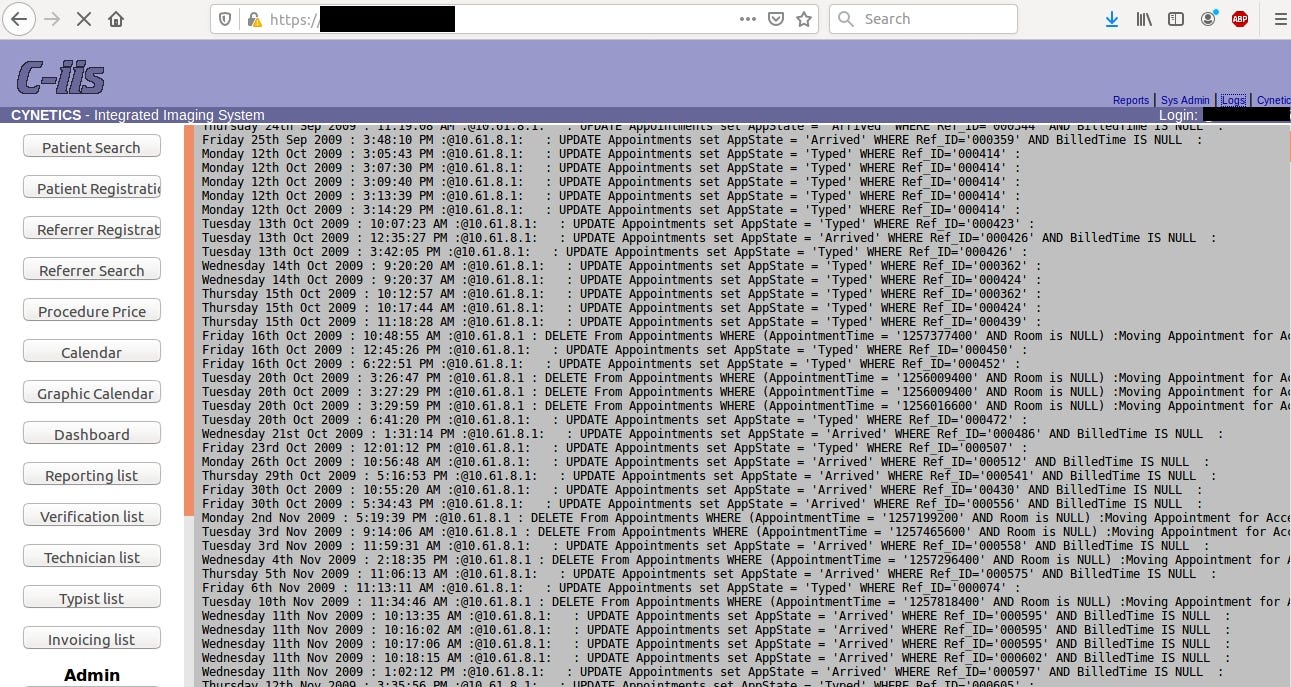

The example of this can be two radiology servers in Australia. From one hand Australia is afraid of Chinese espionage techniques like Cloudhopper but from other they leave two unprotected Cynetics (http://www.cynetics.com.au/) servers. It’s web based Medical Imaging Systems for Clinical reporting & practice management.

Australian Cyber Security Centre has been informed about the leak and servers have been closed. Hovewer, they were accessible for almost a month what allowed to download all of the data by state actors or cyber criminals.

In this case leak contained 4,5 TB of data including radiology photos of pregnancies with diagnosis (almost 2M images!), invoices or personal patient’s data.

It’s worth to mention that servers was so unprotected that gave total admin rights with possibly to hijack logs and even delete patient’s payments and clinical results.

One could wreak total havoc in the server, tamper client’s data, delete payments of all patient’s or find vulnerability in Cynetics web management and penetrate the network deeper.

Payments and debtors details go back even to 2009 and photos to 2016. Probably there are some rules that require to keep medical data for specific period of time.